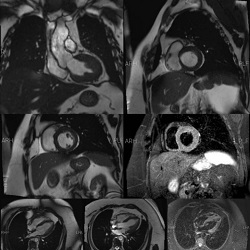

تشخیص بیماری های قلبی و عروقی

دکتر آزاده داودیان متخصص قلب وعروق دارای بورد تخصصی و فارغ التحصیل دانشگاه علوم پزشکی اصفهان می باشند.

Dr. Davodian's cardiology clinic in Borujen provides the following medical services:

Echocardiography, ECG interpretation, pre-surgery consultation, pregnant women's heart health consultation, high blood pressure diagnosis and treatment